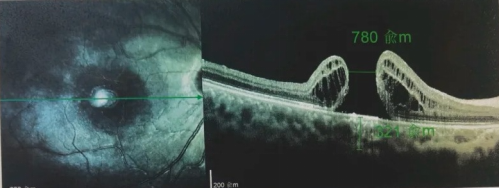

由于自身患有頸椎病,每次術(shù)后長(zhǎng)期的趴睡都讓他痛苦不堪。為了尋求更好的治療,吳爺爺來(lái)到廈門大學(xué)附屬?gòu)B門眼科中心,找到了眼外傷及眼底病2科的李海波博士后。此時(shí),吳爺爺右眼的黃斑裂孔已經(jīng)持續(xù)擴(kuò)大到780μm,演變?yōu)殡y治性的大裂孔。

最讓吳爺爺難以置信的是:術(shù)后只需保持平躺24小時(shí)!第二天復(fù)查時(shí),眼底鏡及OCT檢查清晰顯示——那個(gè)折磨了他大半年的大裂孔,竟然閉合了!且吳爺爺?shù)挠已垡暳τ辛嗣黠@的改善,術(shù)后3天已經(jīng)可以看到 0.15。

黃斑裂孔